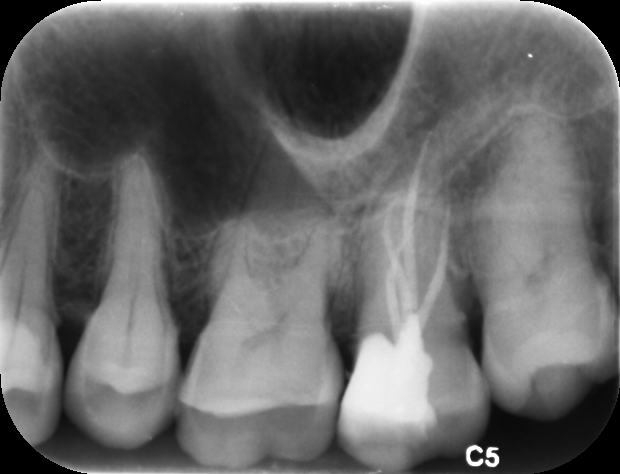

牙片(资料图)

忍无可忍,张女士到口腔机构复诊,医生拆掉牙冠后做了3次根管治疗,但还是酸痛,“吃不好,连续好几天都睡不着,太难受了。”张女士急匆匆来医院看,医师接诊:本来是三条根管,拍牙片看已经充得很完善了,但为什么还会痛?难道是根管治疗也救不了?“我已经种了两颗牙,难道这颗也保不住了?”张女士非常伤心,医生检查之后,决定通过显微镜一探究竟。

果不其然,在显微镜下,还发现了一条被“漏掉”细细的远中舌侧根管,打通了之后,一泡脓流出来了。“为了安全起见,另外三条根管的根充物也要取出来,清理干净,脓流出来之后我就确定问题出在哪了。”医生介绍。找到病根之后,在显微镜辅助下,医生为张女士进行2次根管治疗,将髓腔内的感染组织彻底清除干净,并做根管填充,这颗命途多舛的“病牙”重获新生,也没再发炎,张女士感激不已!